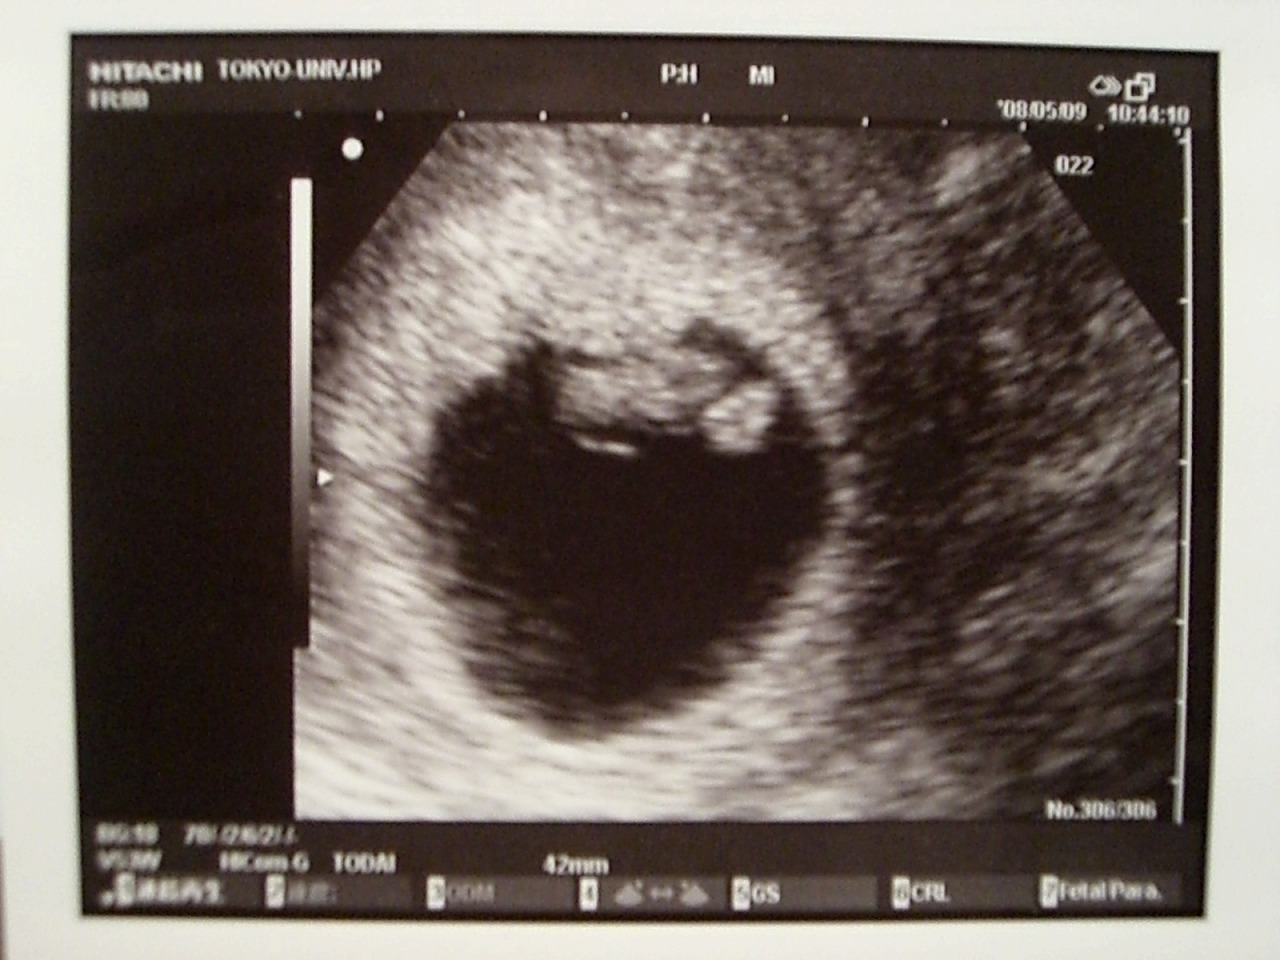

今日は検診日でした♪

まが玉からキューピーになってました!

先生の話だと、ちょぴっと出てきたお手手とあんよをピョコピョコ動かしてた!・・・らしい。

2度目の検診日。

前回「次、心拍確認できなかったら、また流産だね」って言われてたので、エコー見るのが正直怖かったんだけど・・・。

ドドドドドドド

ボボボボボボ??

すっごーく、早くて、力強い心音が聞こえてきました。

今まで、最長10週での流産処置を受けたことがあるんだけど、それでも心音を聞いたのは初めて。

こんなに、力強いんだね!

こんなに感動したことないってくらい、感動しました

「すごく順調ですよ。良かったね。おめでとう」

初めて、聞いたおめでとうの言葉。

恥ずかしくなっちゃうくらい、長くエコーでうつしてくれて、涙があふれて、止まらない。

うれし泣きって、初めてかも。

着替えてる間にも、介助の助産師さんに「良かったですね。おめでとう」と、言われて、

思わず鼻水まで出てしまいました(出しすぎだよっ)

CRL≒1cm

力強い心音で、ワタシをホッとさせてくれた、親孝行な子です。

このままどうか、無事に、すくすく育ってね。

12月にあなたに会えるのを、楽しみにしています。